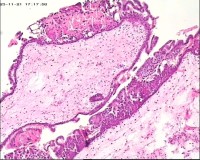

性别

女

年龄

20岁

临床诊断

一般病史

停经3月,阴道不规则流血7天。

标本名称

宫刮物

大体所见

灰白灰红碎组织一堆,大小为7*6*1cm,部分组织呈水泡状

水肿的绒毛和蜕膜,没看到增生的滋养细胞。必要时可做IHC除外部分葡萄胎,并结合临床HCG。

考虑葡萄胎